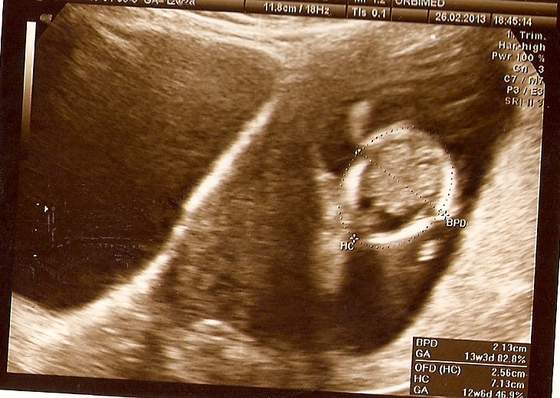

love - ja DOPIERO na 14:30 (ale i tak capnęłam pierwszy numerek, bo lekarz przyjmuje właśnie od tej godziny). Chciałabym, żeby mąż mój w końcu zobaczył i uwierzył

Ale godzina taka, że nie wiadomo czy uda mu się wyrwać z roboty, szczególnie, że następnego dnia mamy sprawę w sądzie i wziął wolne... eh...